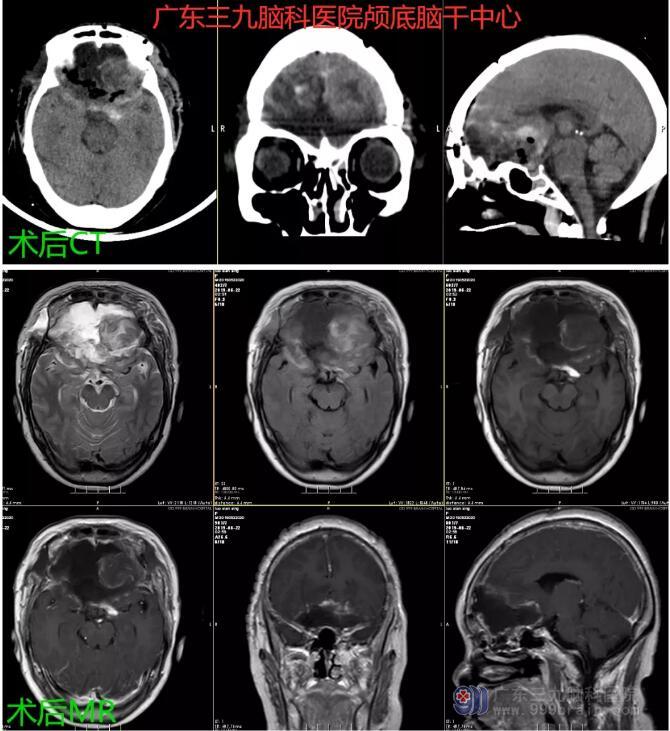

图3:术后CT及MR示前颅窝底占位性病变切除术后改变,原病变已切除